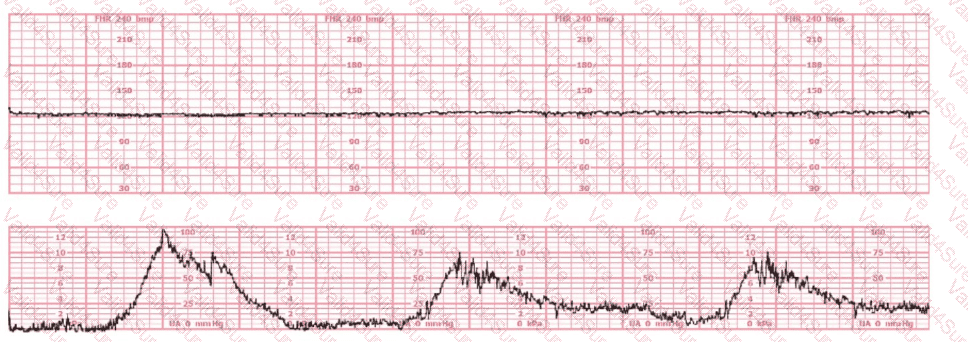

The tracing shown is from a woman at 28-weeks gestation in the post-anesthesia care unit (PACU) after an appendectomy. She is alert and awake. Based on this fetal heart rate pattern, the most appropriate intervention is:

Vibroacoustic stimulation (VAS) is a useful intervention which can